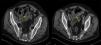

Varón de 67años con antecedentes de mesotelioma pleural maligno (T3N2M0) intervenido en julio 2010, en el que se realizó una pleuroneumectomía radical con linfadenectomía, recibiendo quimioterapia adyuvante y en seguimiento por Oncología. Acude a Urgencias en agosto de 2011 por dolor abdominal de 4h de evolución, de inicio súbito, localizado en el hipogastrio y que posteriormente se hace difuso. A la exploración presenta abdomen con defensa generalizada y signos de irritación peritoneal. La analítica está dentro de los límites de la normalidad. La radiografía de abdomen no presenta hallazgos relevantes y se realiza una TC abdominal con contraste intravenoso que informa de neumoperitoneo, engrosamiento mural circunferencial de un corto segmento de intestino delgado en hipogastrio (yeyuno) con marcados cambios inflamatorios y pequeñas burbujas de aire adyacente (fig. 1). Ante los hallazgos se decide intervención quirúrgica urgente mediante laparotomía media supra-infraumbilical, hallando peritonitis aguda purulenta inframesocólica por perforación única de yeyuno sobre placa isquémica. Se realiza resección intestinal y anastomosis término-terminal manual. El postoperatorio fue satisfactorio, y la anatomía patológica informa de metástasis de mesotelioma maligno epitelioide en la pared intestinal y en 2 ganglios aislados. El paciente fue remitido a Oncología, iniciando tratamiento con quimioterapia.